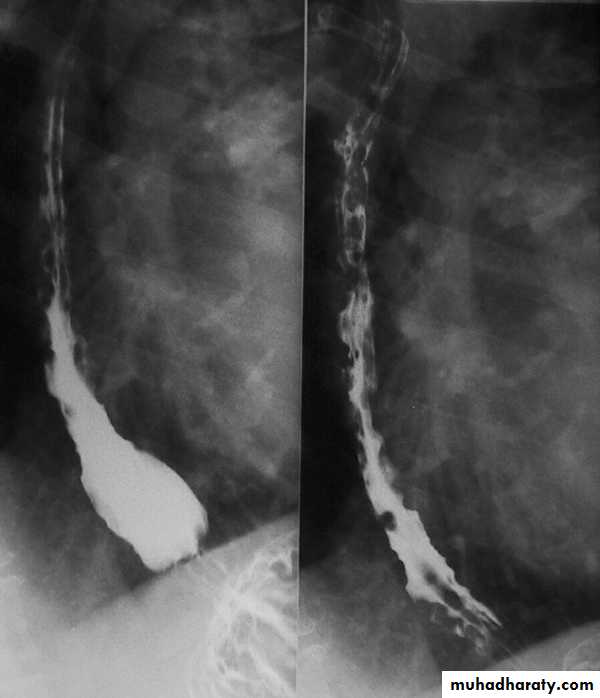

Diffuse esophageal spasm

Diffuse esophageal spasm produces intermittent contractions of the mid and distal esophageal smooth muscle, associated with chest symptoms• Congenital Anomalies